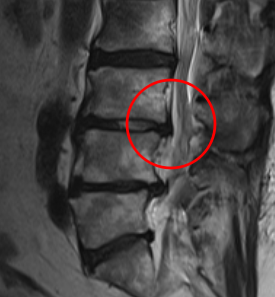

治療後

腰痛や、左臀部下肢外側の痛みと痺れの根本原因であるL3/4の狭窄を取り除く手術「PEL」を施し、神経の圧迫を取り除きました。またこの手術と同時に神経細胞の修復作用効果を期待して、濃縮血小板由来の成長因子を患部に注入する再生医療「PRP療法」を行いました。

術後の翌日には痺れが軽減。痛みは左のふくらはぎに少し残っているとのことでした。1か月後の定期健診では、左のふくらはぎの疼痛も軽減傾向に。手術前よりも腰痛は10から3に、左下肢疼痛は10から1に緩和しました。